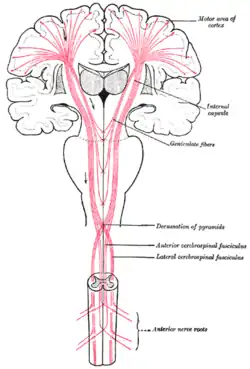

A localização do córtex motor primário é mais óbvia no exame histológico devido à presença das células Betz distintivas. A camada V do córtex motor primário contém neurônios piramidais gigantes (70-100 μm) que são as células Betz. Esses neurônios enviam axônios longos aos núcleos motores contralaterais dos nervos cranianos e aos neurônios motores inferiores no chifre ventral da medula espinhal. Esses axônios fazem parte do trato corticoespinhal. As células de Betz representam apenas uma pequena porcentagem do trato corticoespinhal. Por algumas medidas, eles representam cerca de 10% dos neurônios do córtex motor primário que se projetam para a medula espinhal[2] ou cerca de 2-3% da projeção cortical total para a medula espinhal.[4] Embora as células de Betz não compõem a saída do motor inteiro do córtex, eles, no entanto, fornecem um marcador claro para o córtex motor primário. Esta região do córtex, caracterizada pela presença de células de Betz, foi denominada área 4 por Brodmann.

Caminho

À medida que os axônios motores viajam para baixo através da matéria branca cerebral, eles se aproximam e fazem parte do membro posterior da cápsula interna.

Eles continuam para baixo no tronco cerebral, onde alguns deles, depois de atravessar o lado contralateral, distribuem os núcleos motores do nervo craniano.

Depois de atravessar o lado contralateral na medula oblongada (decussação piramidal), os axônios viajam pela espinha medial como o trato corticoespinhal lateral.

As fibras que não atravessam o tronco encefálico viajam pelo trato corticoespinhal ventral separado, e a maioria deles passa para o lado contralateral na medula espinhal, pouco antes de atingir os neurônios motores inferiores.